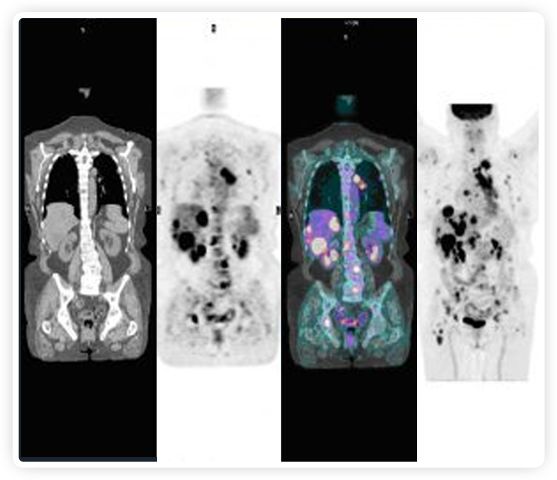

正電子發(fā)射斷層掃描(PET)是癌癥檢測中已建立的成像標(biāo)準(zhǔn),與其他成像方式相比,PET能提供高靈敏度和特異性的圖像。

到目前為止,放射腫瘤學(xué)中(使用的圖像主要是結(jié)構(gòu)性的,而PET圖像可以提供生物學(xué)信息。通過使用注射示蹤劑,例如18-FDG,PET可以描繪腫瘤的代謝活性,使其“點亮”。(FDG是用于可視化癌癥代謝的最廣泛使用的示蹤劑。與正常組織相比,腫瘤細胞保留更高水平的FDG。)不同的PET示蹤劑可以識別腫瘤的不同生物學(xué)特征,例如特定生物標(biāo)志物抗原(例如,PSMA)或甚至探測免疫系統(tǒng)本身(例如,PDL1表達或活化的T細胞)。